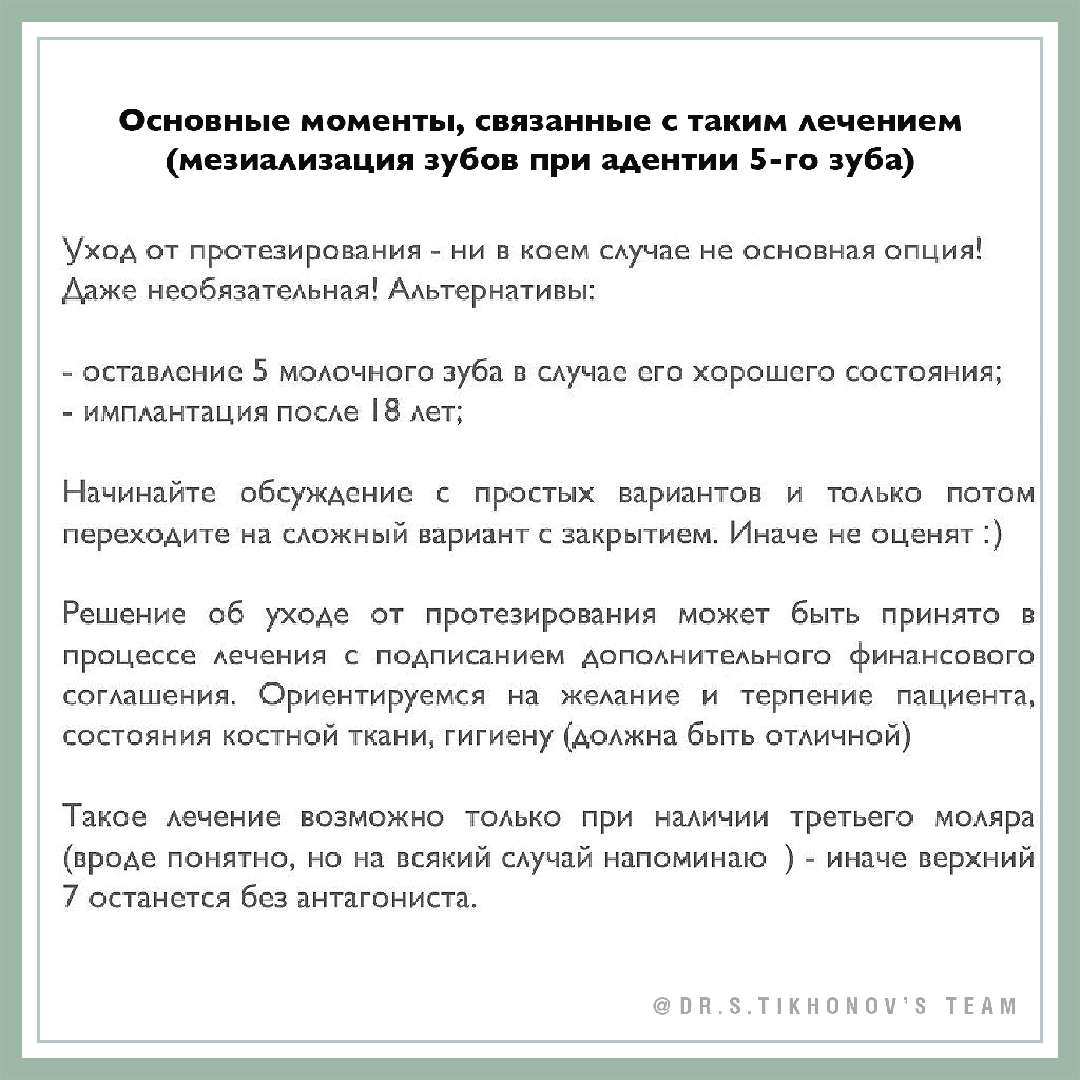

Уход от протезирования при адентии 5 зуба у подростка

Пациенту Алексею - 18 лет на момент начала лечения, и это его желание - уйти от протезирования.

В целом, условия были благоприятные - терпеливый и позитивный пациент, готовый к длительному лечению. У пациента также был скелетный 3 класс, так что лечение включало камуфляж мезиального прикуса.

Общая продолжительность лечения - 3,5 года, непосредственный срок закрытия пространства - 23 месяца. Это довольно типичные цифры для корпусного (!) мезиального перемещения трех моляров на нижней (!) челюсти. Общие советы для коллег по такому лечению на слайдах к статье.

Подробности механики с минивинтами на семинаре Андрея Викторовича по винтам. Он очень крутой - семинар! Андрей – тоже!:)